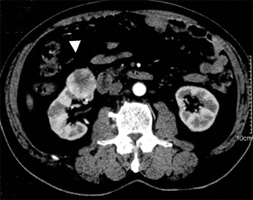

通常、診断は造影剤を使ったCT検査にて可能です(図)。また、3D-CTでは通常のCT検査をコンピューター処理し腎臓の血管の走行、栄養動脈の確認を3次元で確認することが可能です。主に術前検査で行われ、手術時の血管処理の貴重な情報になります。

| 図)腹部造影CT(➡腫瘍) | 図)3D-CT(➡腎動脈) |